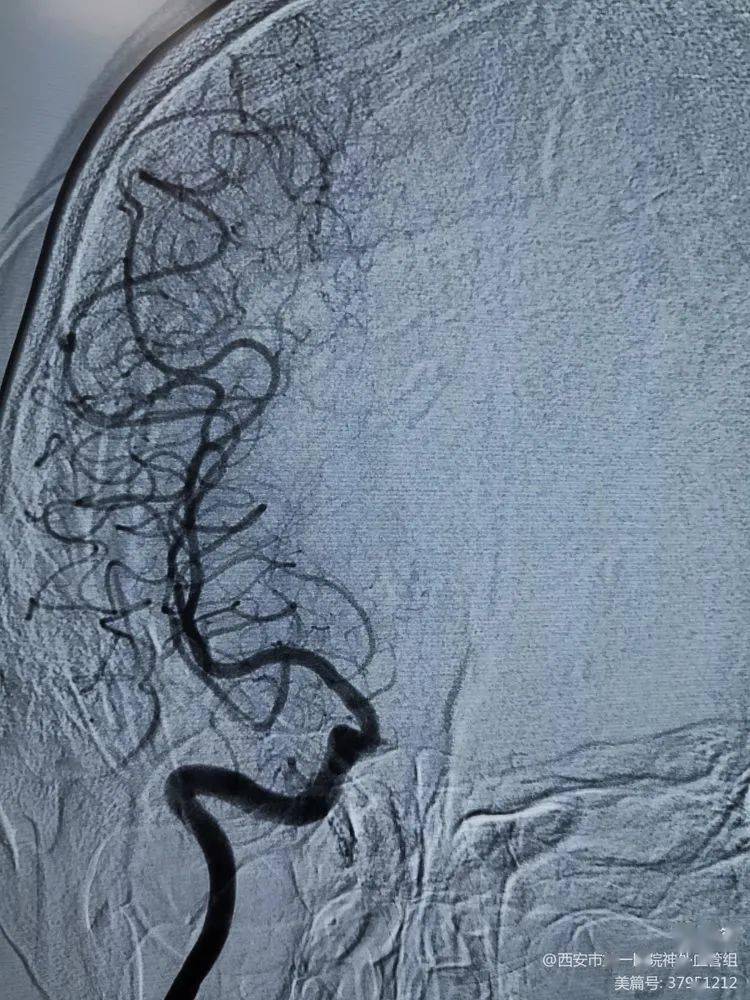

14床,彭长启,基底动脉狭窄,右椎v4闭塞